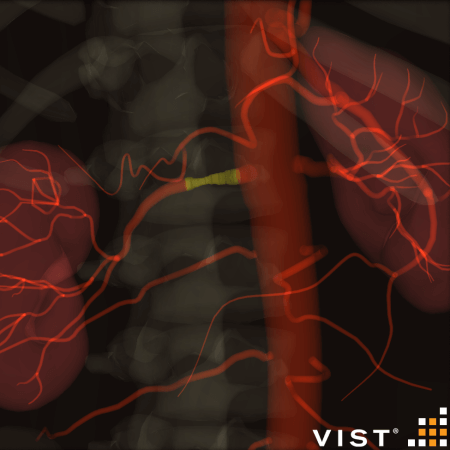

Flow Diverter Case planning in Ankyras®

Import Case directly into VIST® simulator

Practice deployment in patient-specific anatomy